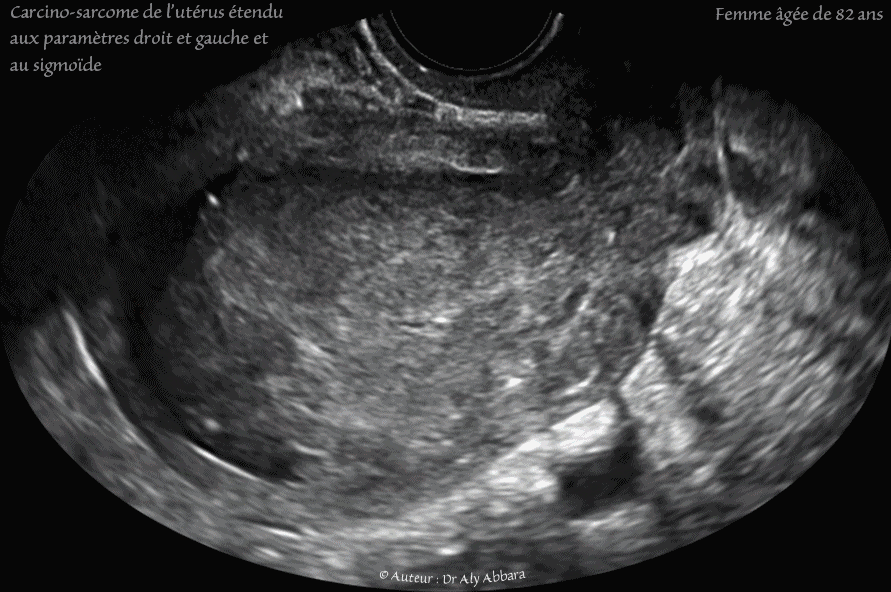

Images échographiques animées montrant l'utérus d'une femme âgée de de 82 ans, atteint d'un carcino-sarcome sous forme d'une tumeur solide de 66 x 42 x42 mm de diamètre (61 cm3) occupant la cavité du corps utérin, puis de son isthme et du canal cervical.

Une grande masse de (85 mm de grand axe), solide, évoluant dans le paramètre droit ; elle est de même nature anatomo-pathologique (carcio-sarcome).

Une grande masse latéro-utérine gauche mesurant (121 mm de grand axe), mixte (solide avec quelques composantes kystiques) de même nature anatomo-pathologique (carcio-sarcome), évoulant aux dépens du sigmoïde.